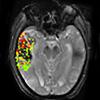

August 19, 2016 — The detonation of atomic bombs over the Japanese cities of Hiroshima and Nagasaki in August 1945…